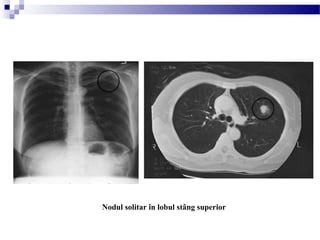

Rx torace, inciden a PA i profil: Nodul pulmonar solitar la nivelul lobului superior stângț ș

Nodul solitar în lobul stâng superior